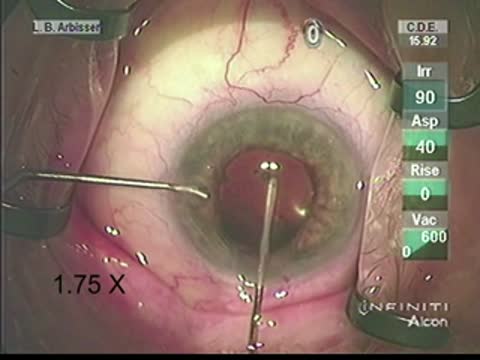

Be Prepared for Surprise Zonulopathy

Lisa Brothers Arbisser, MD